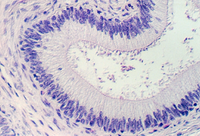

Below is another view of a large (excretory) duct of a salivary gland showing the mucin in Goblet cells after a special stain. What might be the advantages of an epithelium that has a basal cuboidal cell layer and an apical columnar cell layer?